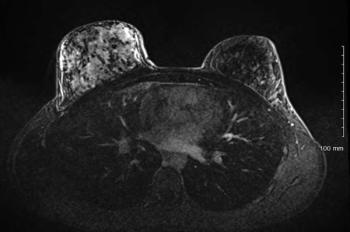

A 38-year-old woman presents with dyspnea and general malaise. Diagnostic imaging revealed the presence of multiple bilateral cystic and nodular lesions in her lung. What is your diagnosis?